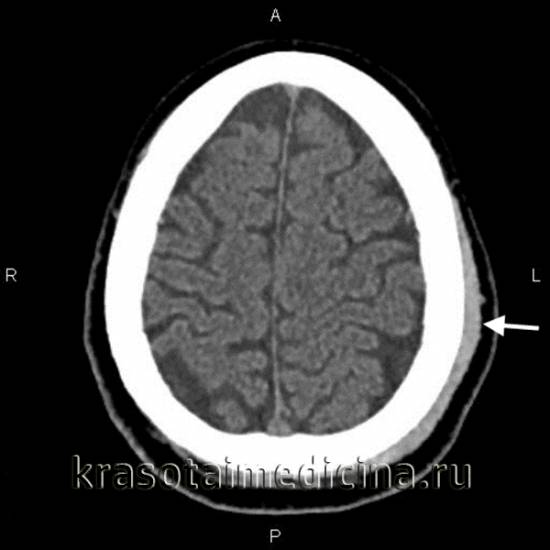

image

КТ ОГК. Гиперденсное скопление крови в толще мышечного массива грудной стенки справа, окруженное зоной отека.